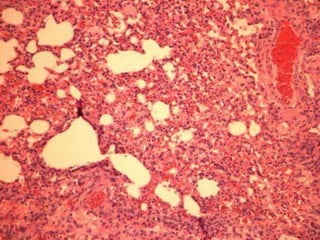

Lung tissue samples (1918)

1918 influenza AFIP lung block

Extract RNA, sequence, clone the virus

Pathological specimen (circa 1918)